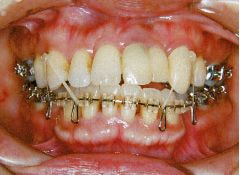

治療例2 (補綴処置+矯正)